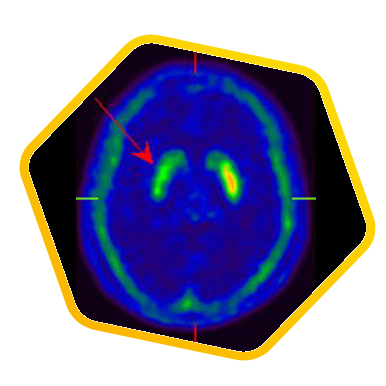

脑神经科

![]() [C-11] Raclopride |

![]() [F-18] DOPA |